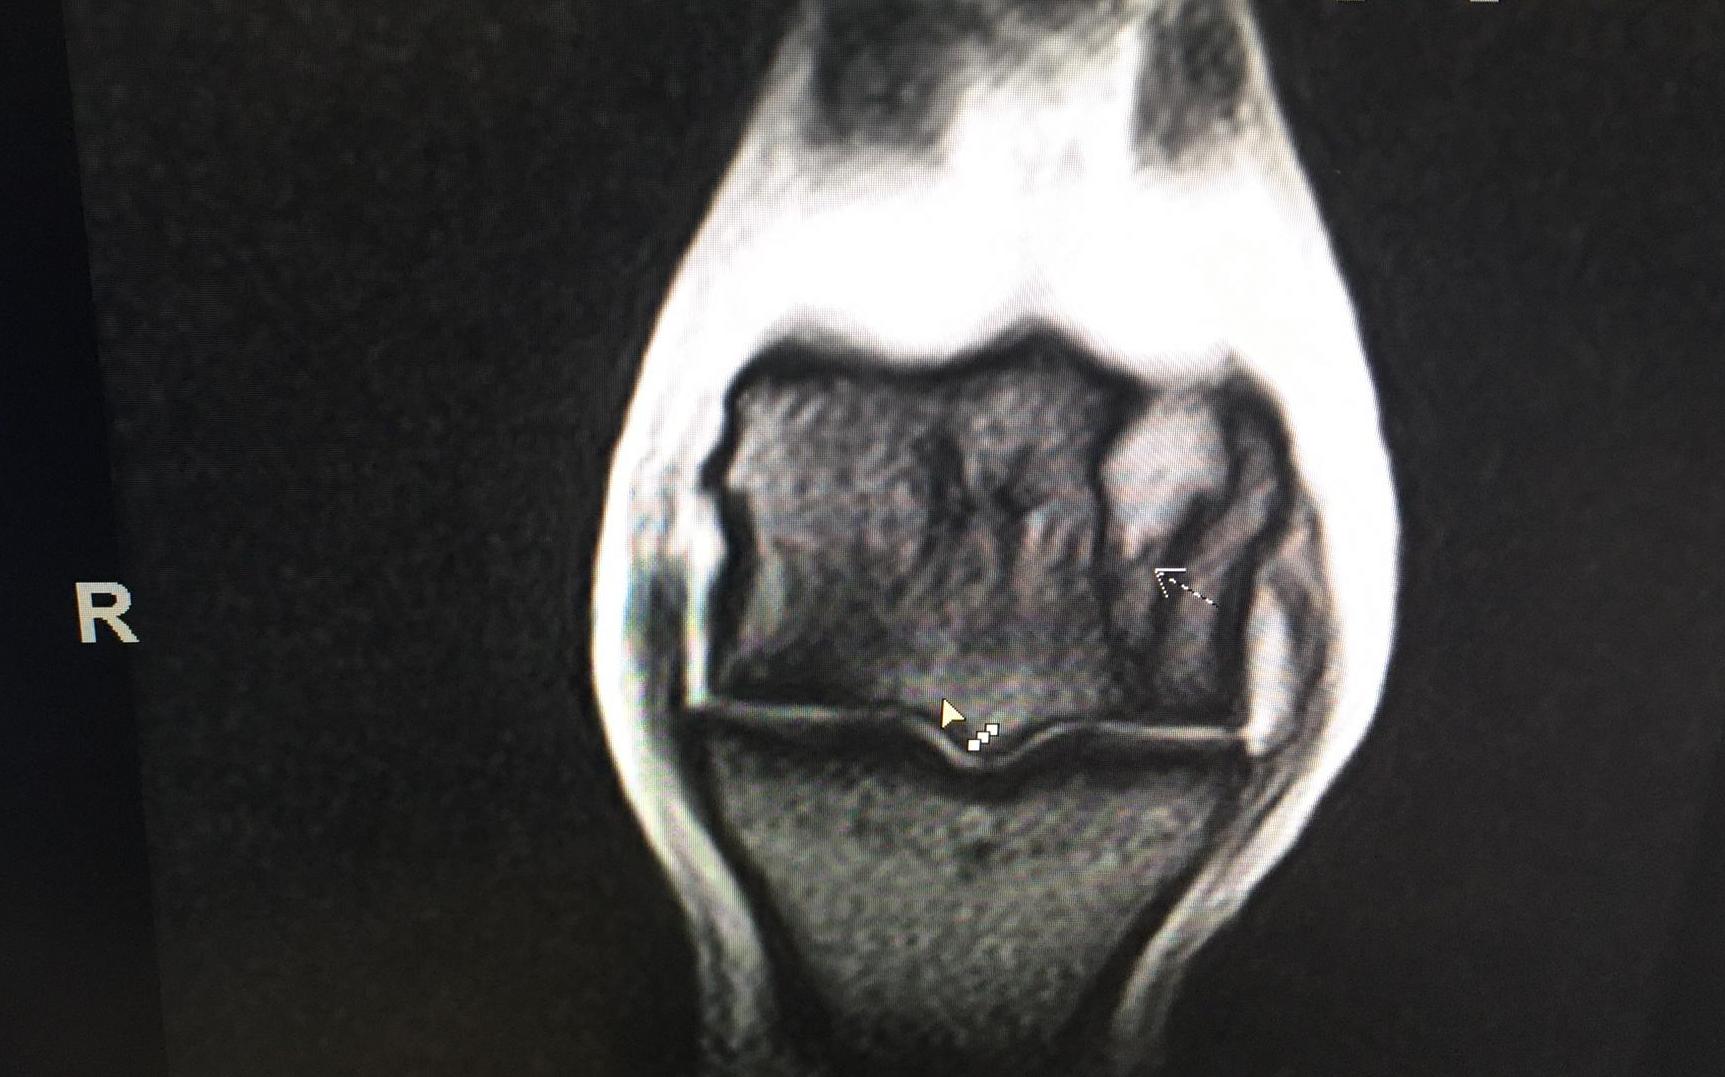

Heute gilt die ganze Aufmerksamkeit VESSILLO. Bei ihm wurden leider am letzten Dienstag Verletzungen festgestellt, die einen operativen Eingriff notwendig machten. Auf den Röntgenbildern war rein gar nichts zu sehen. Doch eine eingehende MRI-Untersuchung brachte es an den Tag: Zwei Fissuren und ein Mini-Ödem (ein Kleinst-Bluterguss im Knochen) ganz unten im Röhrbein, beim Fesselgelenk. Zum Glück hatten wir insistiert und diese Untersuchung gemacht. Sonst hätte es ganz böse enden können.

Das eine MRI-Bild...

...und von anderer Seite.